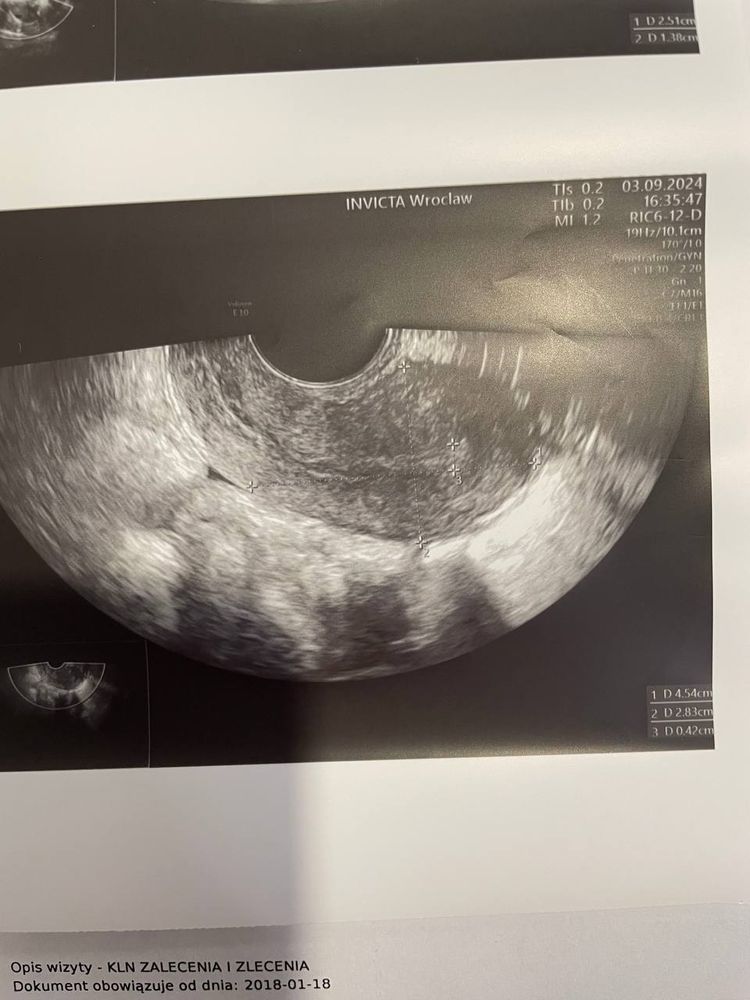

Эндометрий 4,2 мм

В правом яичнике визуально около 5 фолликулов ( в этом срезе )